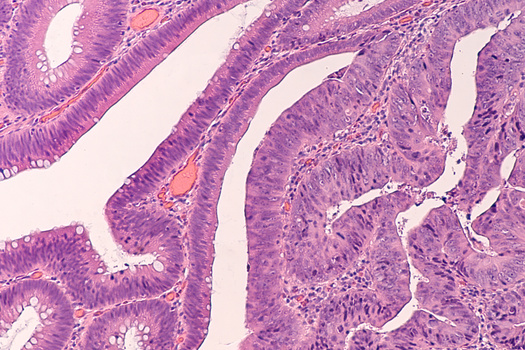

Колоректальный рак чаще всего развивается из полипа. Это образование можно заметить на колоноскопии. Чтобы превратиться в рак, полипу обычно нужно около 10 лет. Если полип удалить, то это предотвратит развитие рака. Для регулярных проверок также используют тест на скрытую кровь в кале. Кровь может появиться в кале из-за полипов или непосредственно рака кишечника. При этом невооруженным глазом ее не заметишь.

(3) Колоноскопия